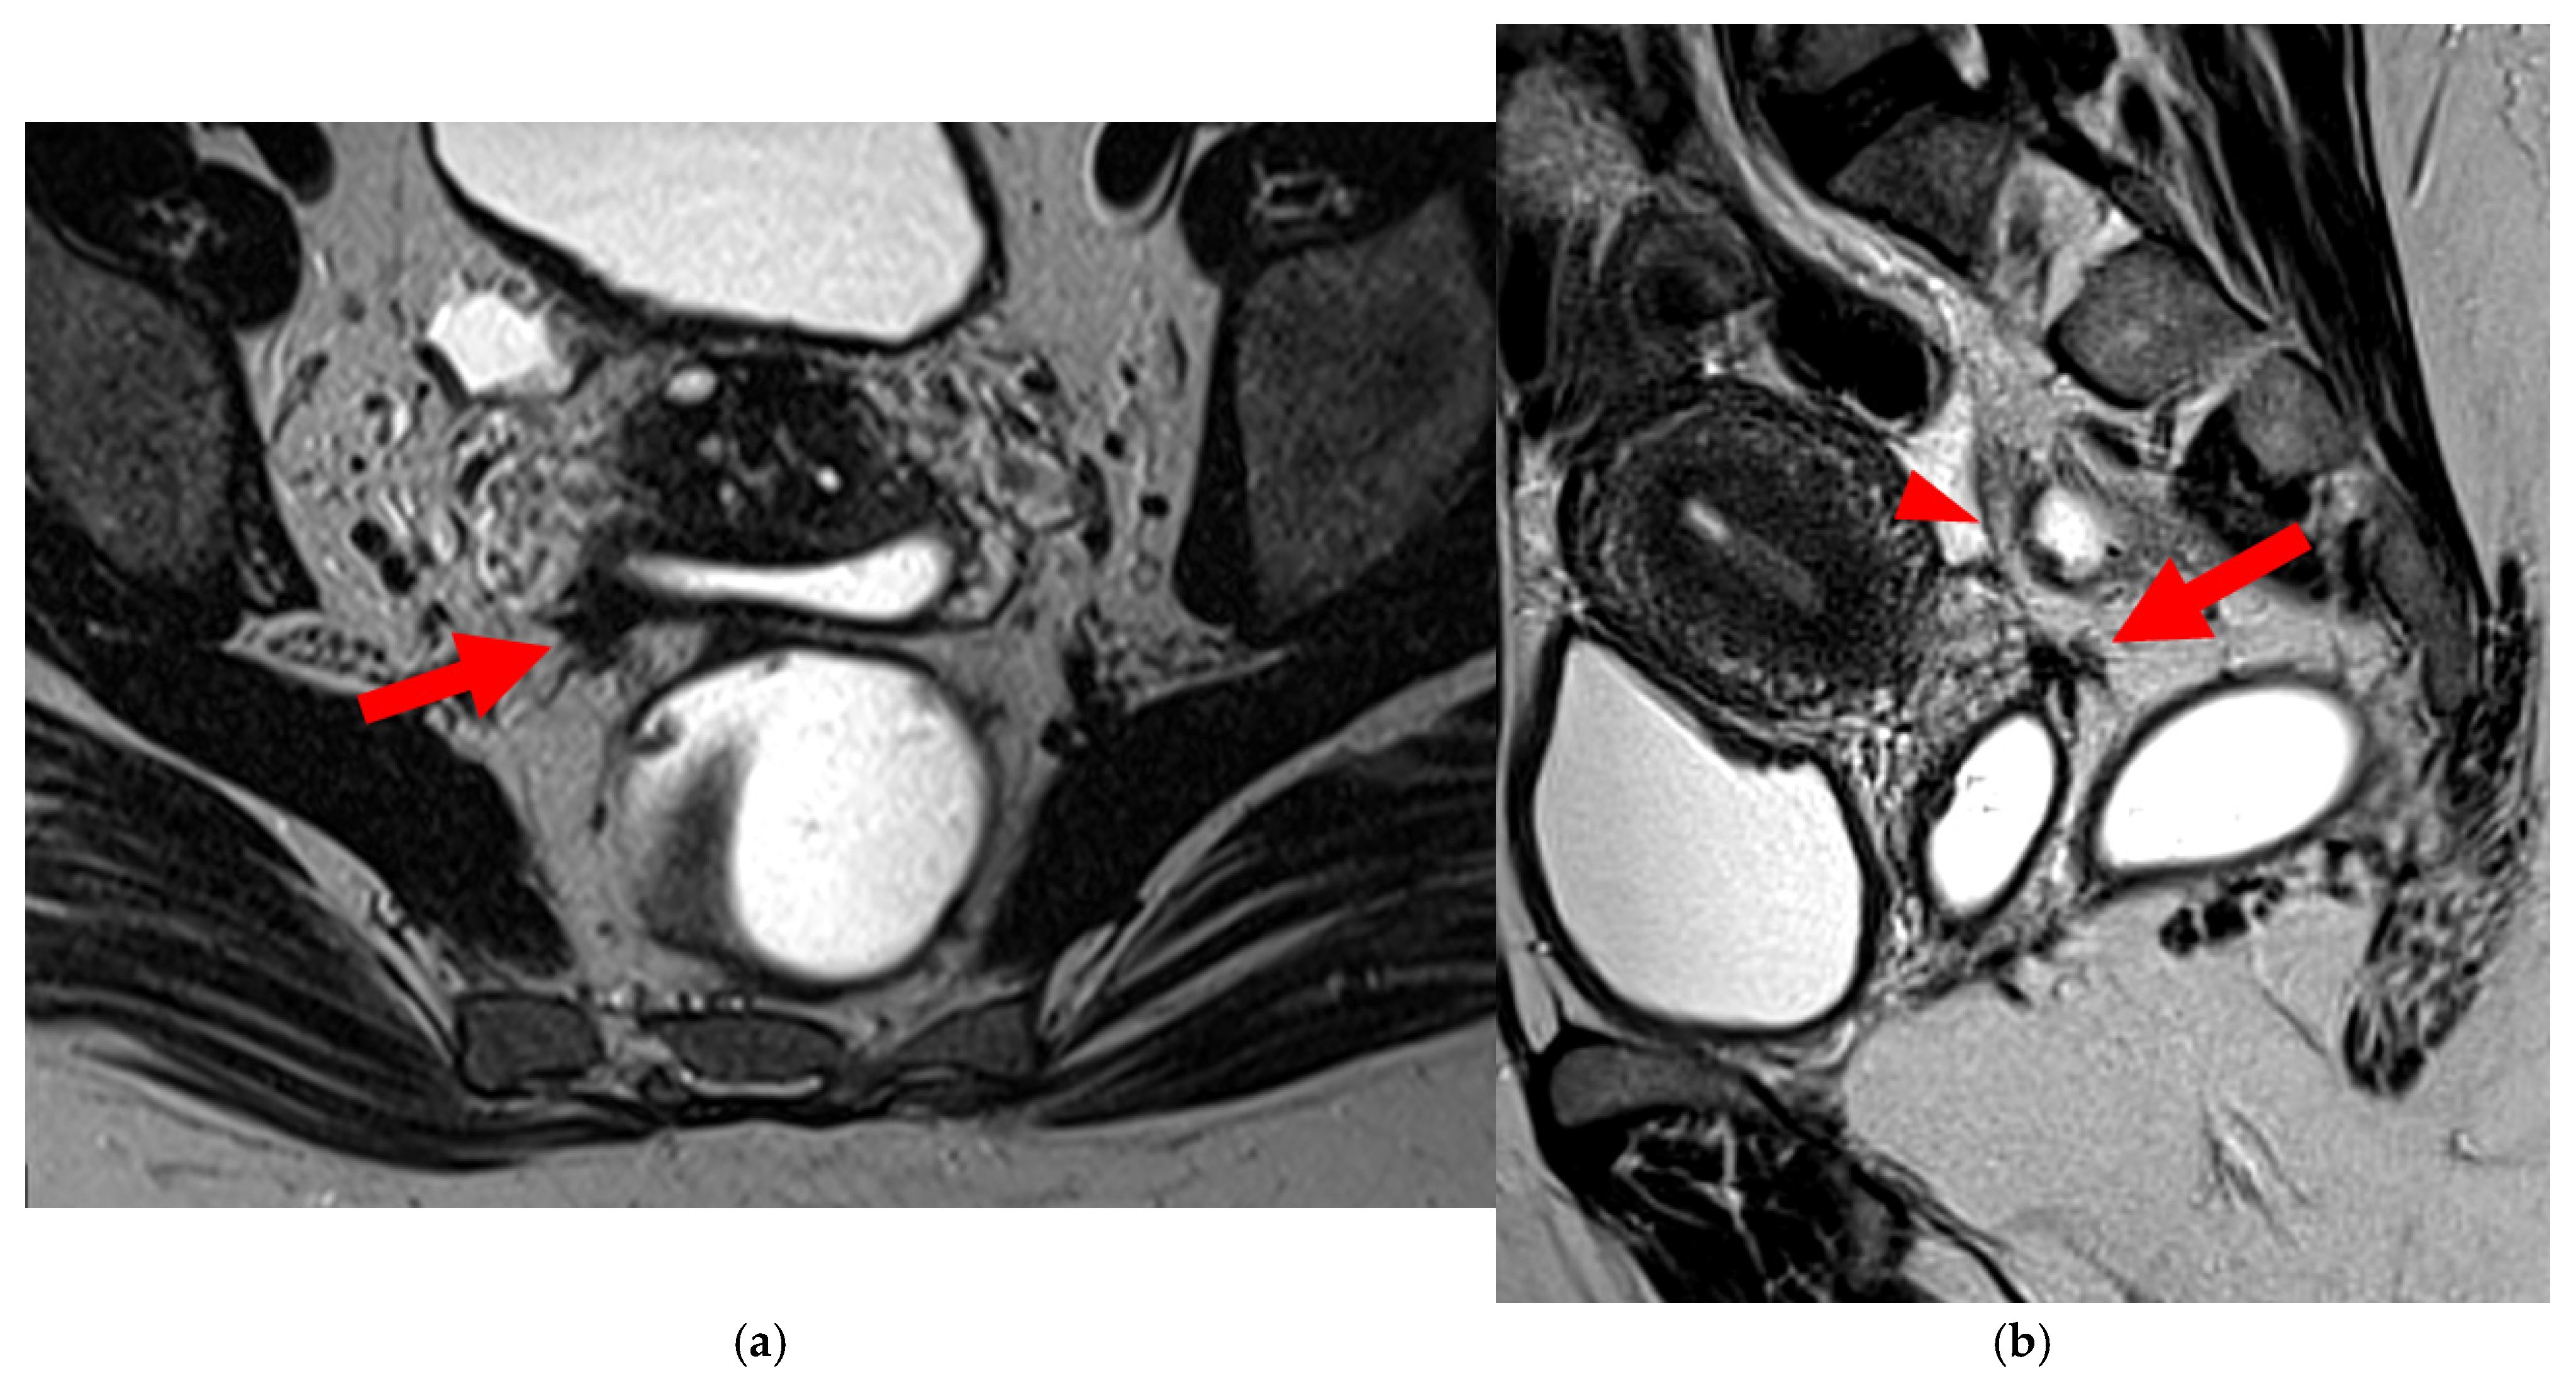

A type 5A USL (Figure 6) is nodular with a smooth contour.

Figure 6. Pelvic MRI scans of two patients with HTD type 5A USLs. (a,b) Sagittal T2WI: nodularity with regular margins (arrows) within the right USL (arrowheads).